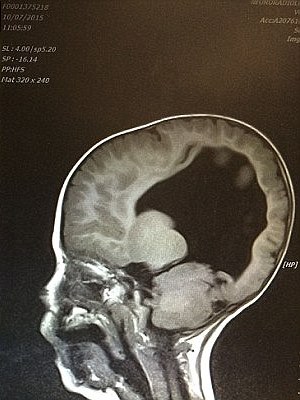

When Noah was born, he only had 2% of his brain and the family was worried about his development. Over the span of several years, however, Noah’s brain miraculously kept on growing and so did the boy.

At the age of three, the boy’s brain has already developed to 80% capacity, and at the age of six, the boy is already able to talk. The 6-year-old fighter is now hoping to master walking, skiing, and surfing!